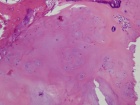

26 year old female with ten year history of right knee pain with intermittent swelling